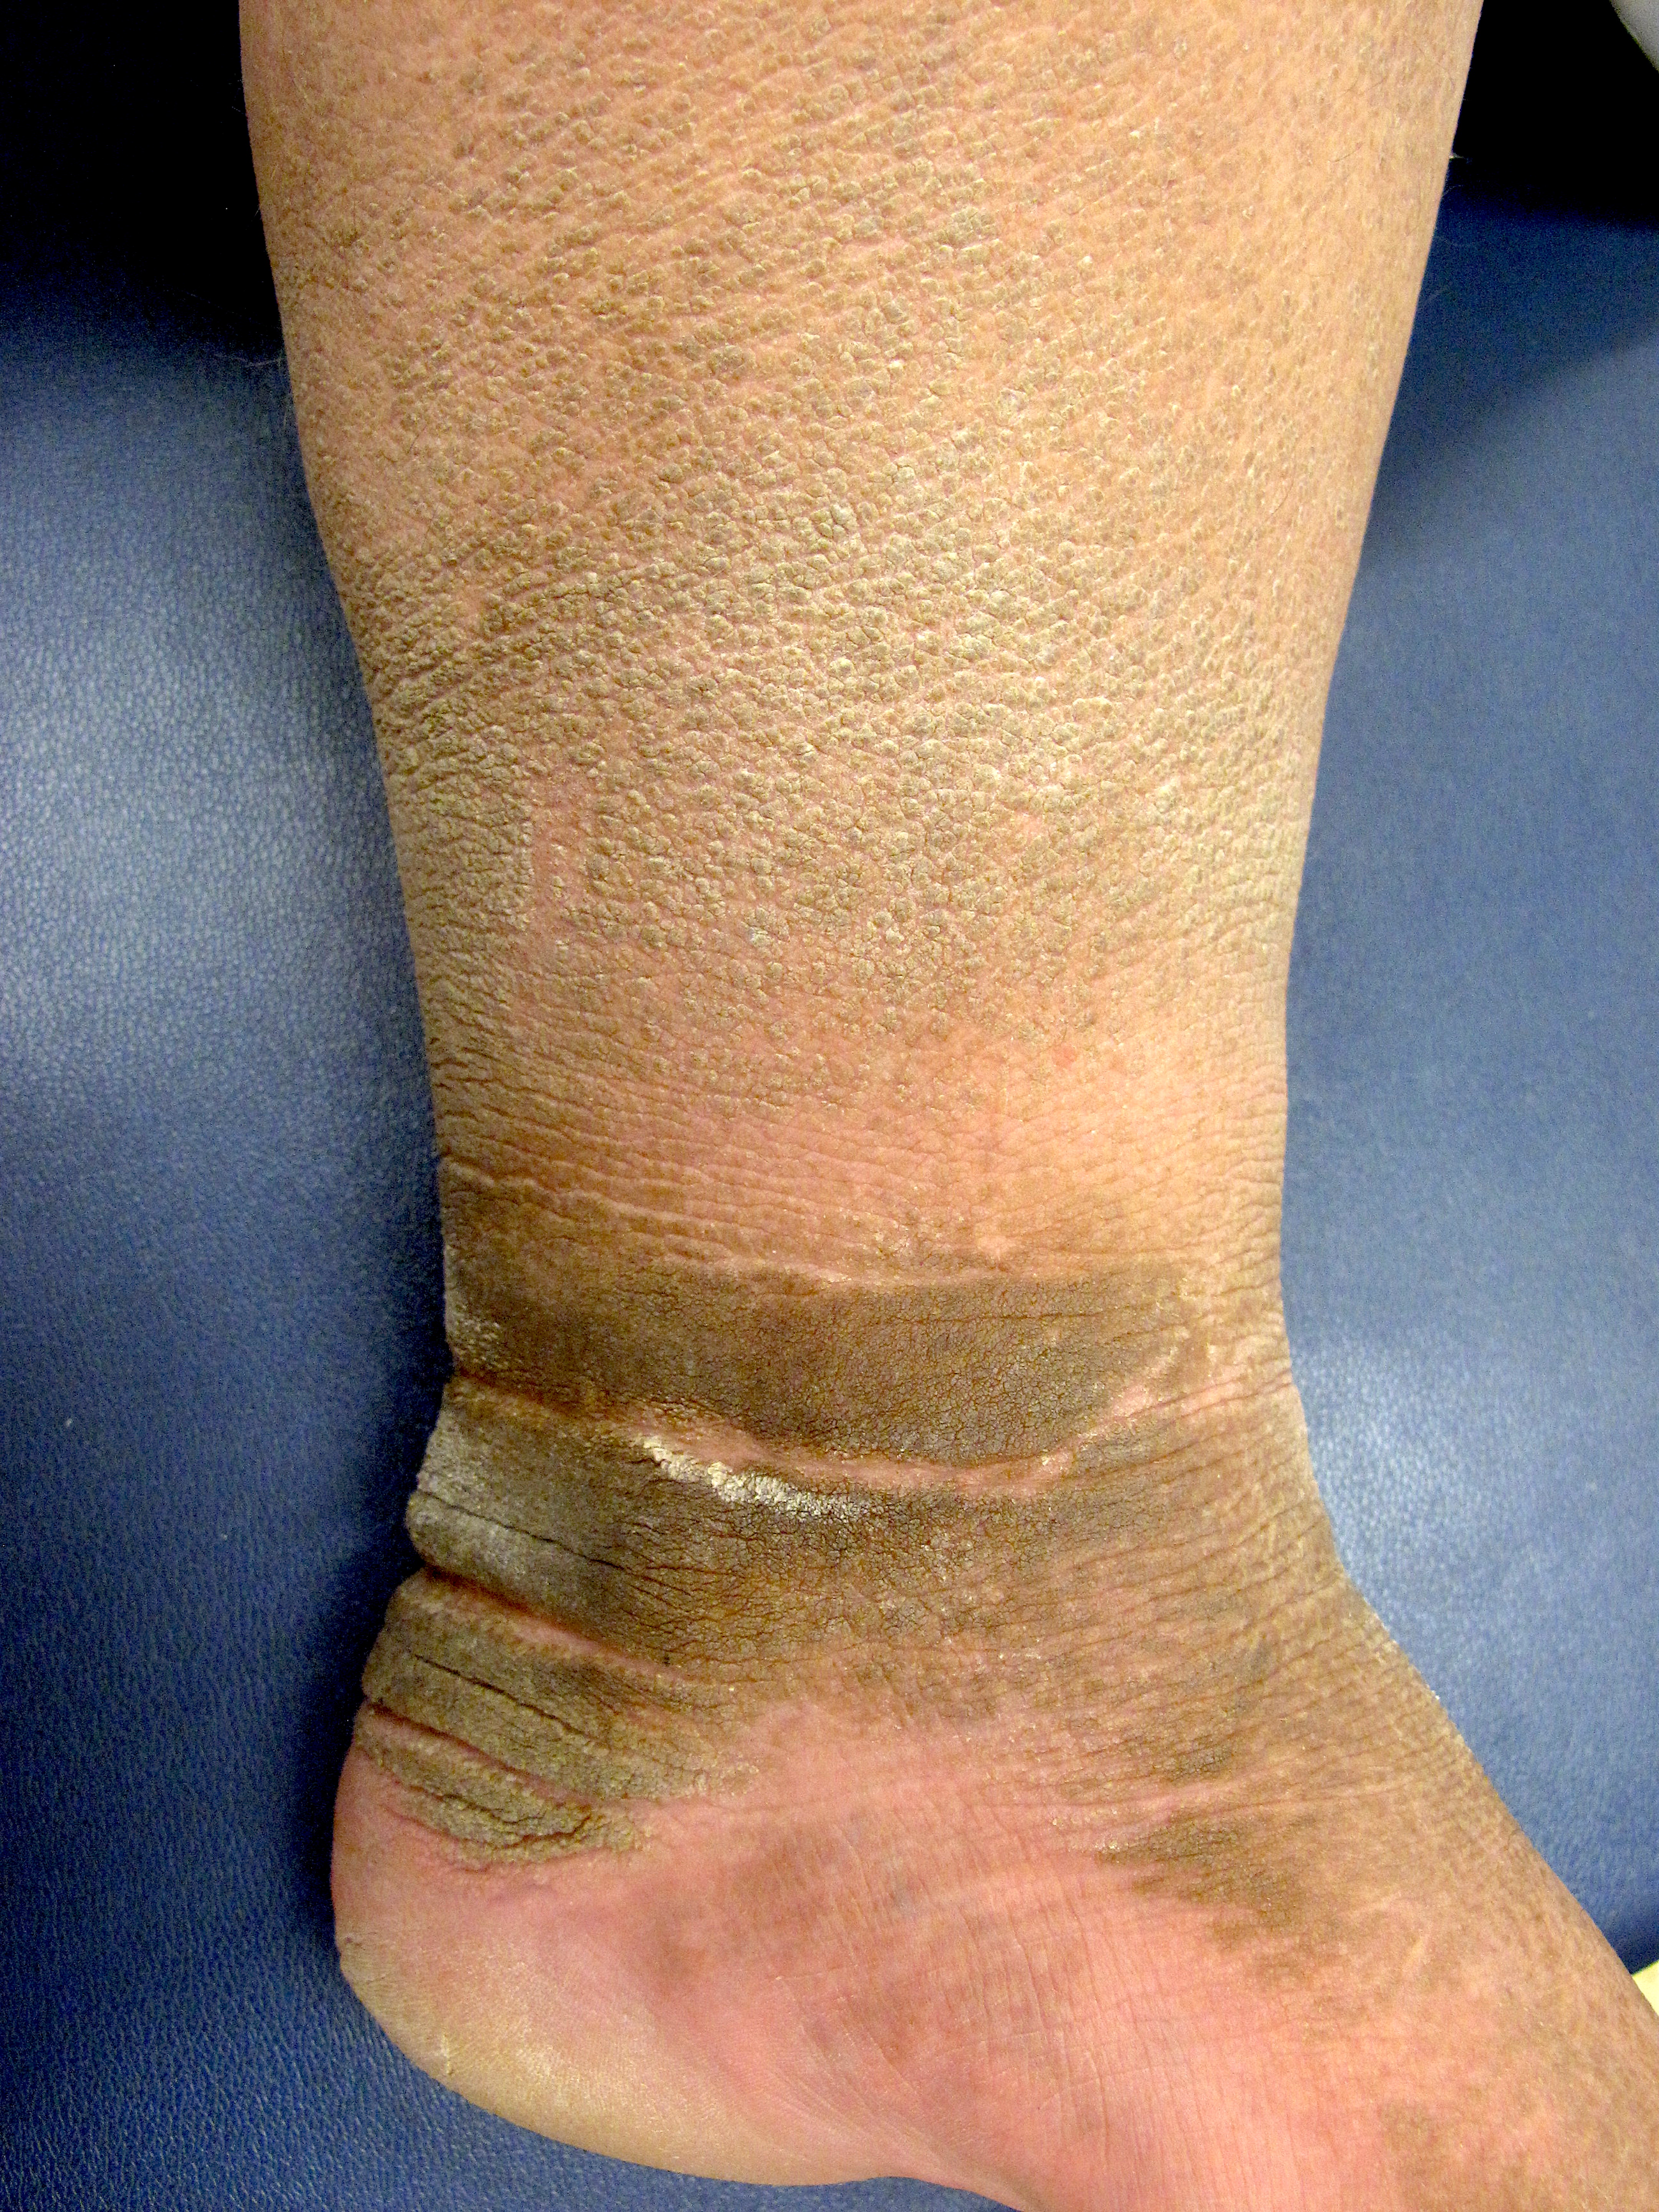

On physical examination, the patient had hyperpigmented velvety plaques involving his neck, back, axillae, dorsal hands, antecubital fossae, ankles, and feet (Figures 1-3). Additionally, there were hundreds of skin tags involving much of the axillary tissue and inguinal folds, as well as some scattered on the thighs.

Figure 3. Thick tan/gray velvety plaques on the right leg and ankle.